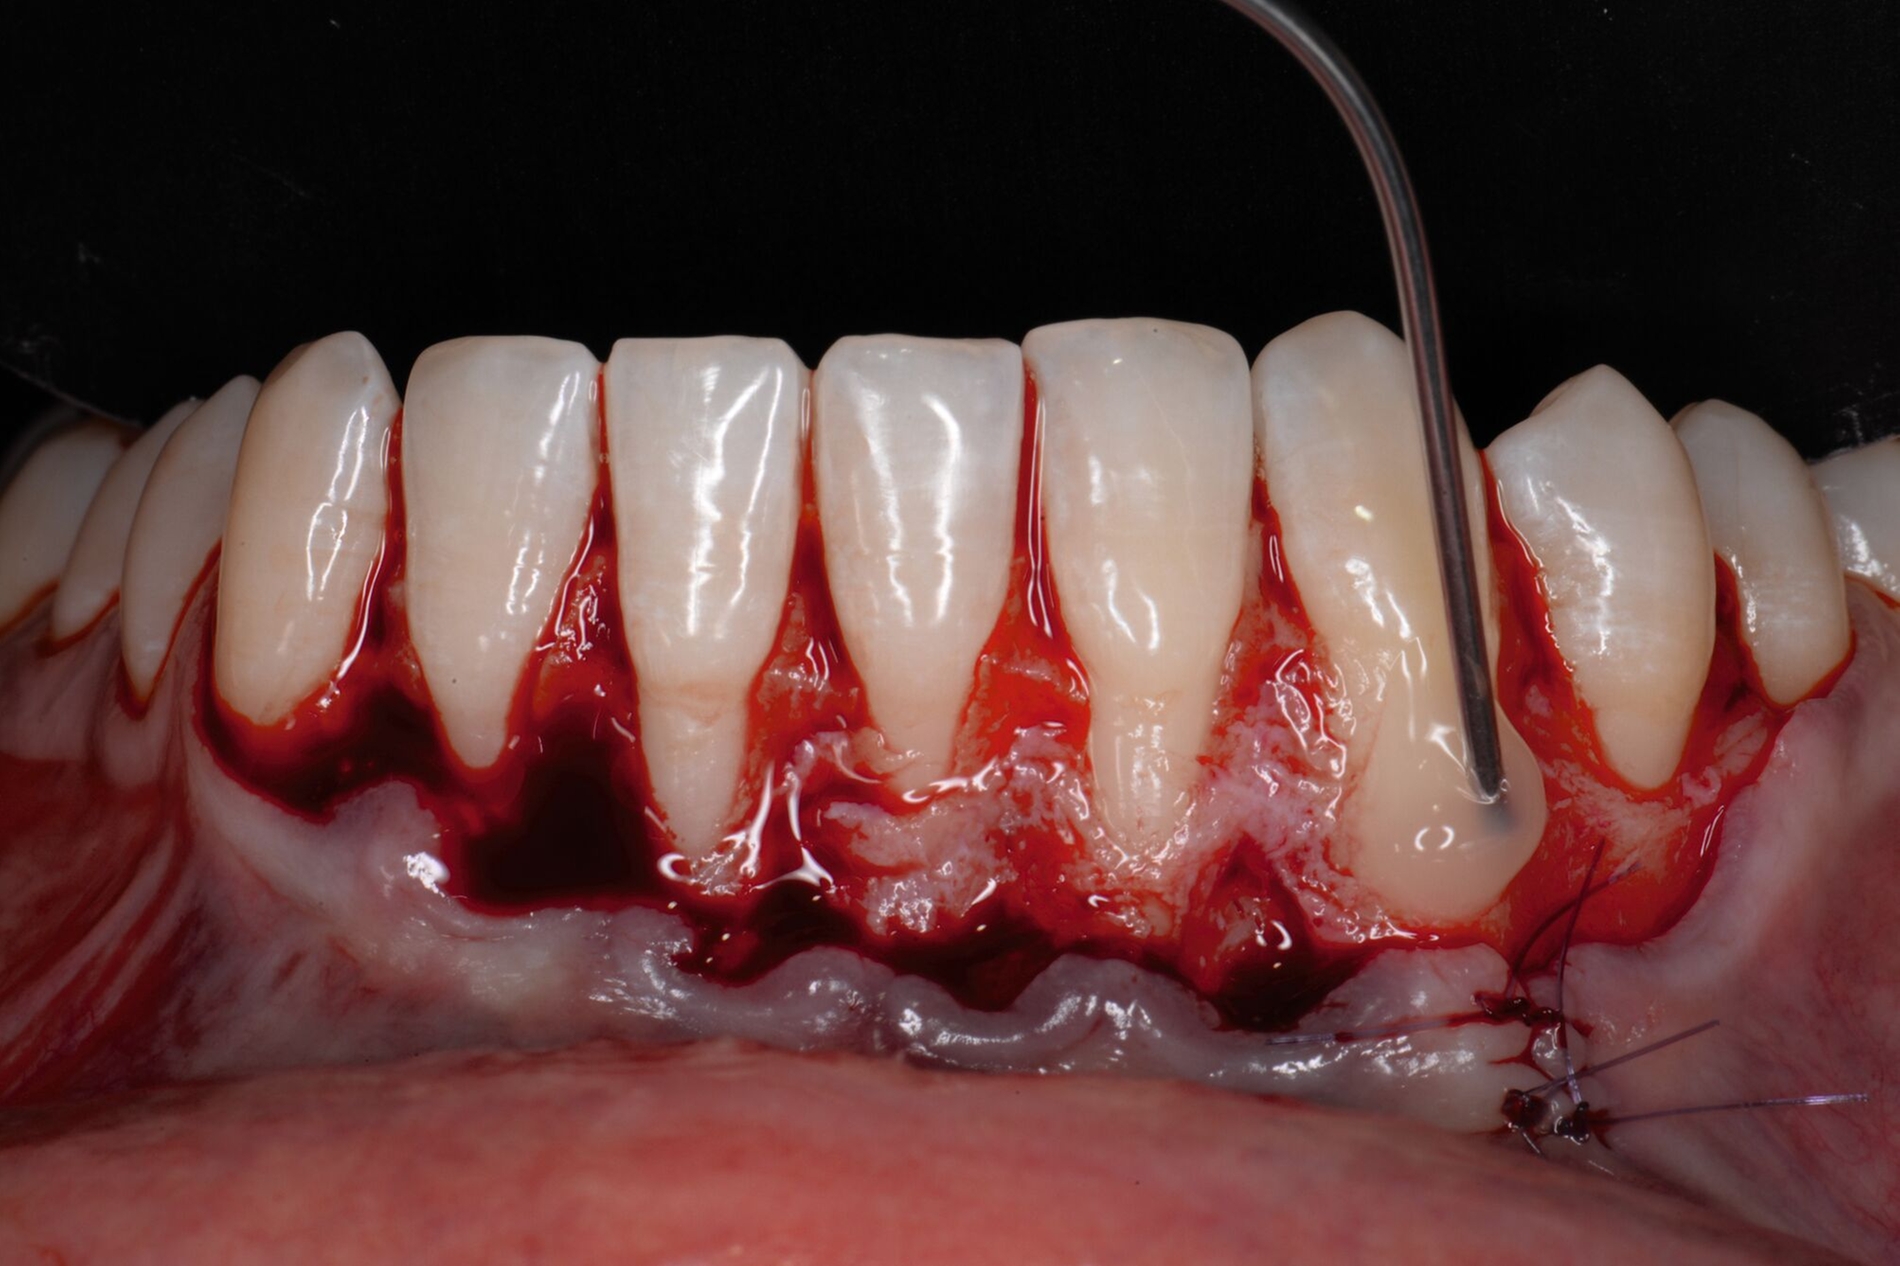

Das Vorgehen ist hier wie folgt: Zunächst wird im Bereich der tiefen Rezession der Gingivarand geringfügig exzidiert, um ein Zusammenwachsen der geschlossenen Lappenanteile zu ermöglichen. Anschließend wird der Schnitt in horizontaler Richtung durch leicht bogenförmige Schnittführungen auf Höhe der Schmelz-Zement-Grenze erweitert, um mindestens zwei Zähne rechts und links von der Rezession (Abbildung 3b). Im Unterkiefer-Frontzahnbereich, wo die Rezessionen heutzutage am häufigsten vorkommen, sollte der Lappen mindestens von Eckzahn zu Eckzahn gebildet werden, um ein harmonisches Ergebnis nach Abheilung zu erreichen. Auf vertikale Entlastungsinzisionen kann komplett verzichtet werden. Anschließend erfolgt die Lappenpräparation nach dem bereits für koronale Verschiebelappen gängigen Prinzip teilschichtig-vollschichtig-teilschichtig.

Die Papillenbereiche werden mit dem Skalpell scharf vom Periost abgelöst. Dann wird das Periost durchtrennt und bis zur mukogingivalen Grenze ein vollschichtiger Lappen gebildet. Nach Überschreiten dieser wird wieder zweischichtig präpariert. Hierdurch wird eine gute Mobilisation des Lappens erreicht, die eine ausreichende Koronalverschiebung ermöglicht. Entgegen dem in früheren Jahren propagierten komplett teilschichtigen Vorgehen, kann durch dieses Verfahren die Gefahr von Lappenperforationen signifikant gesenkt werden, da diese insbesondere im Bereich der mukogingivalen Grenze auftreten. Nachdem die Lappenareale mesial und distal der Rezession gelöst sind, können diese durch zwei bis drei feine monofile Nähte miteinander verbunden werden (Abbildung 3c). Sobald durch diese Naht ein zusammenhängender koronaler Verschiebelappen entstanden ist, werden die Papillenbereiche koronal des gebildeten Lappens entepithelialisiert. Nach Entnahme eines Bindegewebstransplantats oder entepithelialisierten freien Schleimhauttransplantats wird die Wurzeloberfläche mit EDTA-Gel konditioniert und anschließend werden Schmelz-Matrix-Proteine aufgetragen (Abbildung 3d). Diese bewirken die Bildung eines new attachment und fördern zudem die Wundheilung, was gerade bei den delikaten lateralen Verschiebelappen von Vorteil sein sollte [McGuire und Cochran, 2003; Almqvist et al., 2011; Thoma et al., 2011; McGuire et al., 2016]. Anschließend wird das Transplantat durch Nähte ausgehend vom oralen Papillenbereich fixiert (Abbildung 3e). Zuletzt wird der Lappen mit sogenannten doppelten Umschlingungsnähten im Bereich der Papille durch Zug nach koronal und oral fixiert, was eine perfekte Positionierung ermöglicht [Zuhr et al., 2009] (Abbildung 3f). Hierbei muss darauf geachtet werden, dass der Lappen die Schmelz-Zement-Grenze um mindestens 2 mm überdeckt, um eine hundertprozentige Wurzeldeckung erwartbar zu machen [Pini Prato et al., 2005].

Der Lateral Geschlossene Koronal Verschobene Lappen ermöglicht eine annähernd narbenfreie Deckung singulärer parodontaler Rezessionen durch Verzicht auf vertikale Entlastungsinzisionen (Abbildung 3g). Das Lösen der Papillen im Rahmen der Verschiebung ermöglicht eine deutliche Anhebung des Lappens und somit durch großzügige Überdeckung das Erreichen vollständiger Wurzeldeckungen. Durch den lateralen Verschluss im Rahmen der tiefen, über die mukogingivale Grenze hinausgehenden Rezession kann keratinisierte Gingiva im Bereich dieser hergestellt und eine übermäßige Mobilisation und damit Einschränkung des Vestibulums verhindert werden.